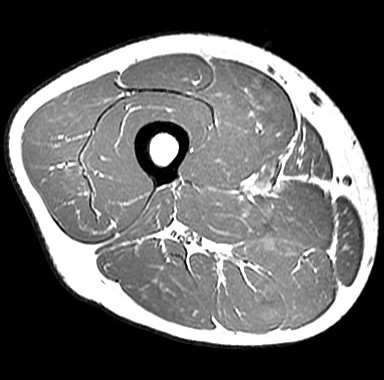

Wir messen die Grösse der Muskeln und wie stark sie sich während einer Kontraktion verändern (Dehnung) mittels Magnetresonanztomographie (MRT).